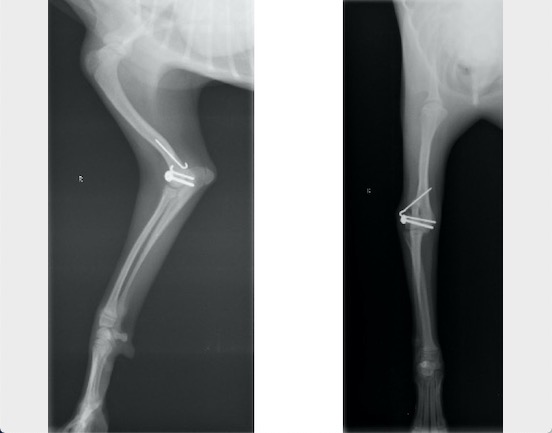

単純X線検査を実施したところ、上腕骨遠位外顆骨折が認められ、上腕骨遠位の成長板をまたぐ骨折であったことから成長板骨折(Salter-Haris Type4)と診断して外科的処置を実施しました。

背掌像より上腕骨遠位外顆の骨折が認められました

内外側の上腕骨顆を皮質骨スクリューとキルシュナーワイヤー、外側上顆をキルシュナーワイヤーにて固定しました